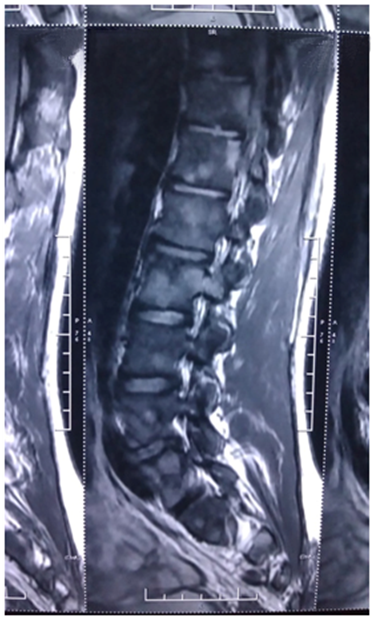

CECT chest and abdomen revealed nodular infiltrates with fibrotic bands in apical segment of right upper lobe with few rim enhancing necrotic lymph nodes at pre-tracheal, right para-tracheal, pre carinal and sub carinal region. Bone marrow examination was done which was normal. Lymph node biopsy of pre-tracheal nodes was done which showed caseous necrosis and langhans type giant cells (Figure 3).

Figure 3 Lymph node biopsy of pre-tracheal nodes was done which showed caseous necrosis and langhans type giant cells.